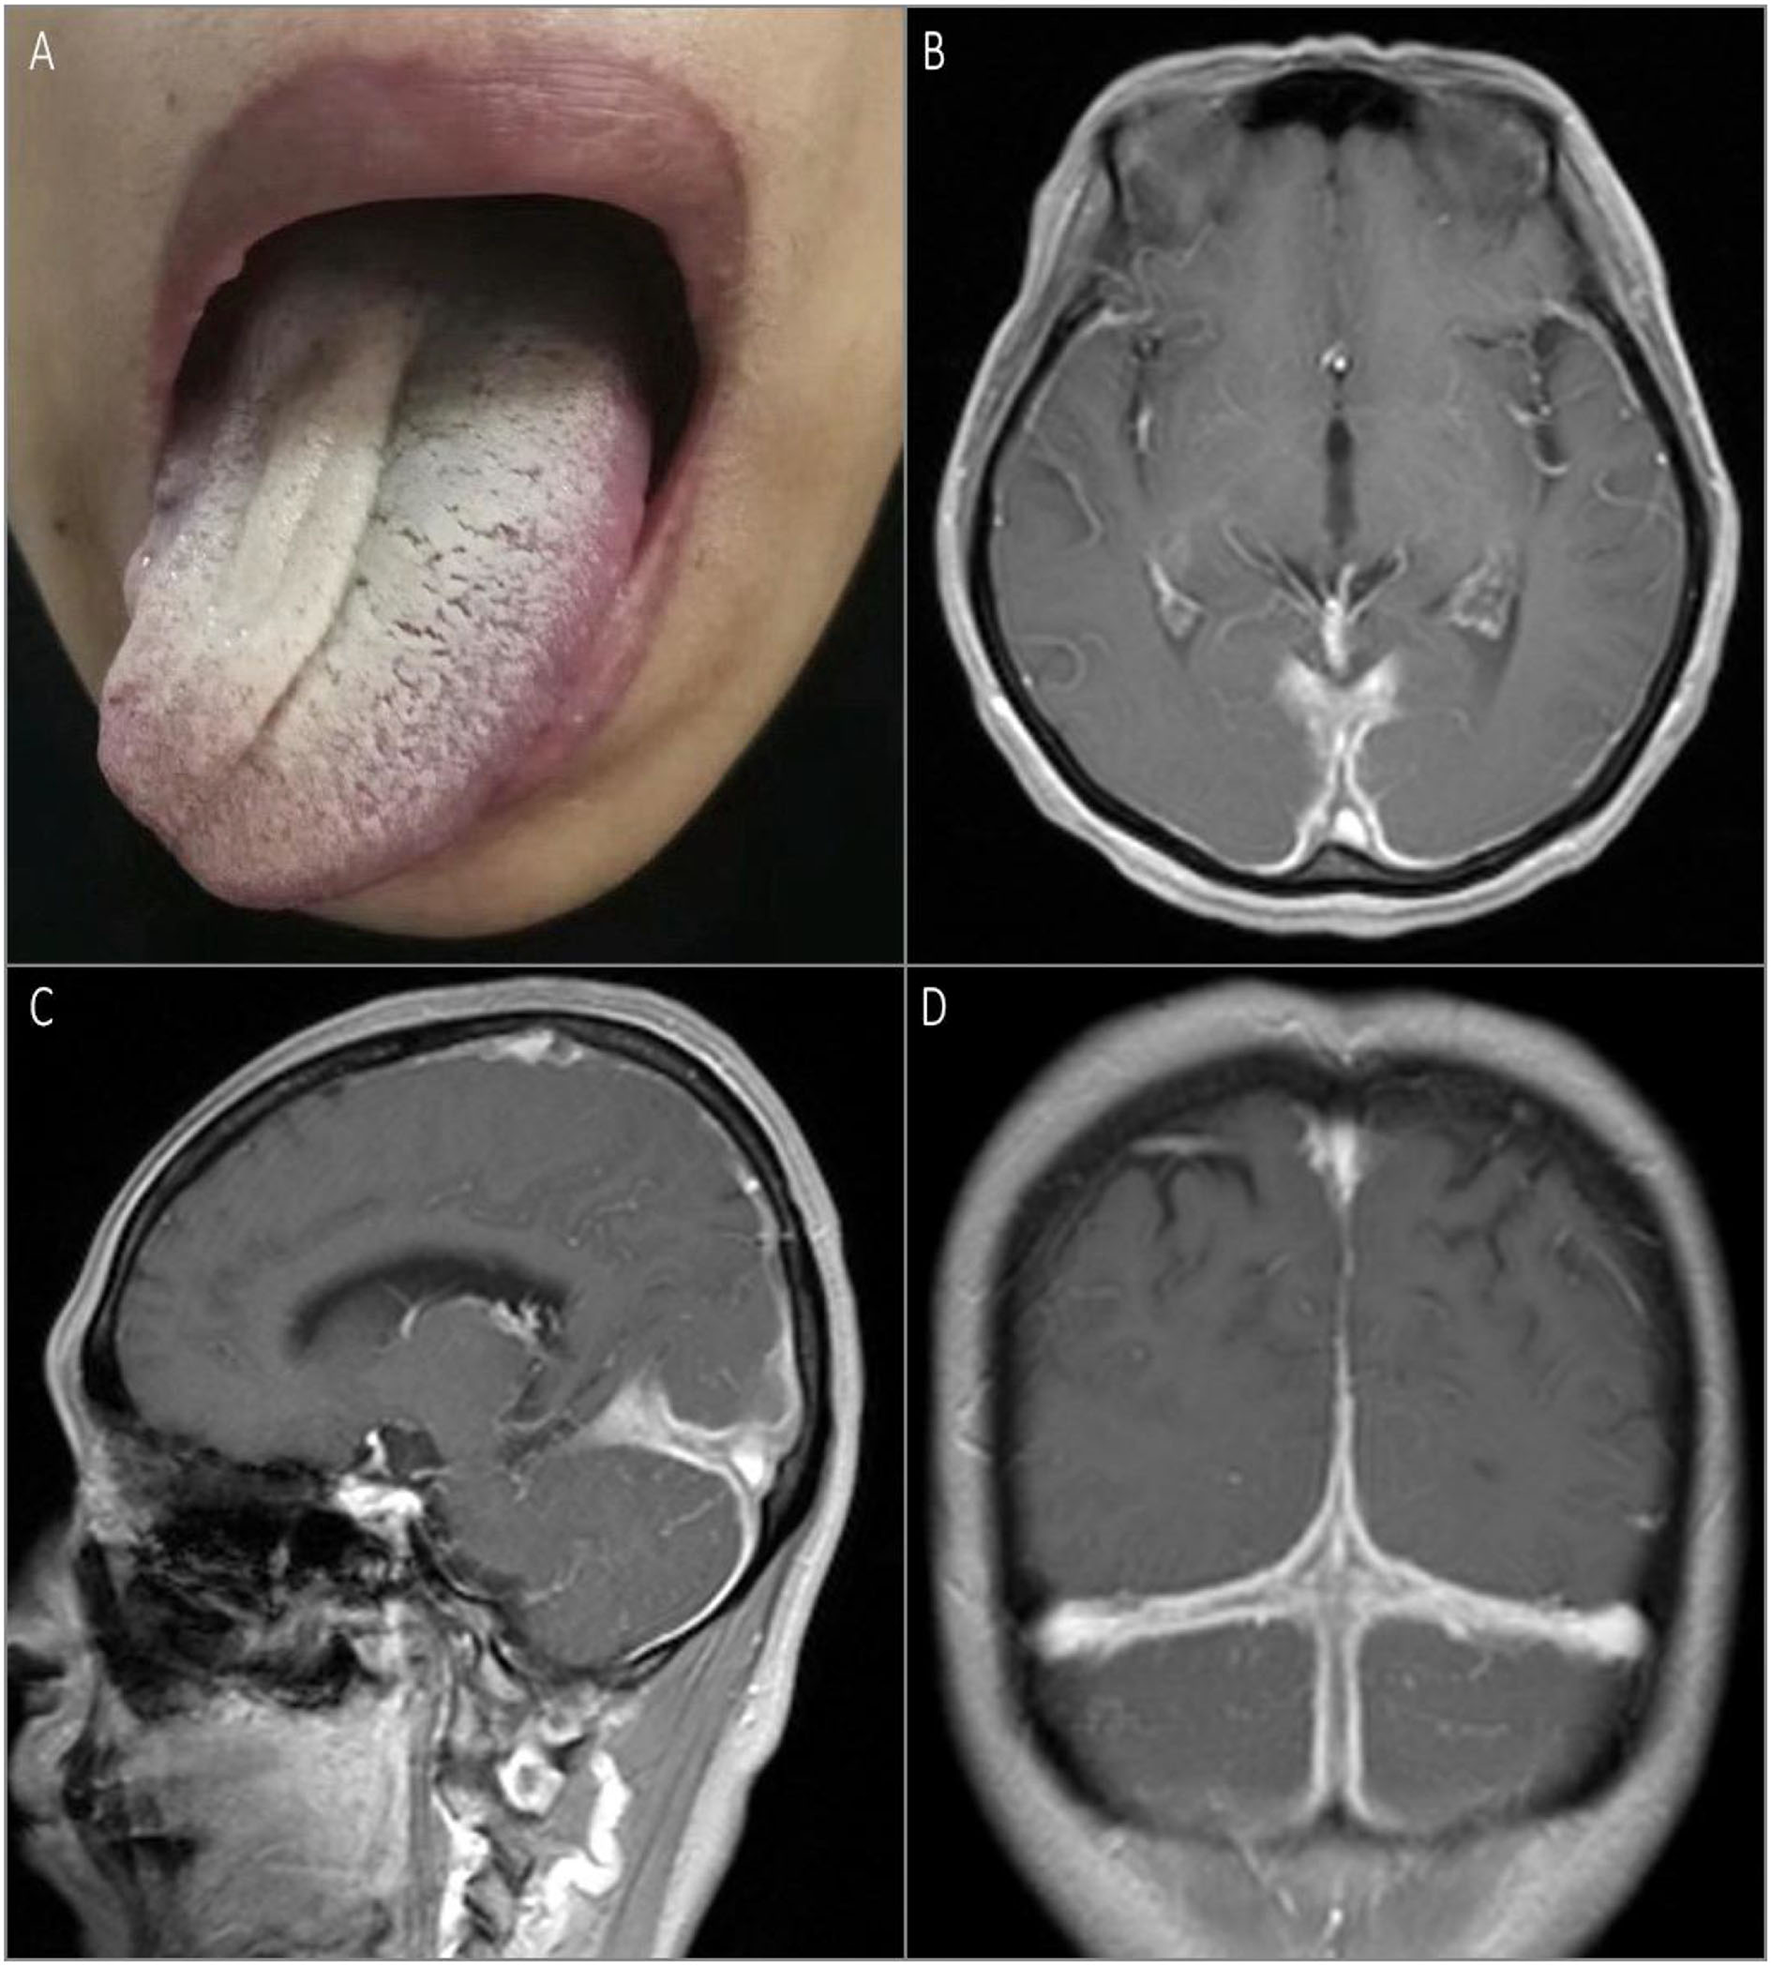

The second patient was a 52-year-old previously healthy woman with an ingravescent occipital headache for 6 months. The only notable neurological examination result was a right hypoglossal nerve palsy (Figure 2A). The gadolinium-enhanced brain MRI revealed pachymeningeal enhancement and thickening, predominantly in the posterior fossa and bilateral posterior cerebral hemispheres (Figures 2B–D). Infection tests were negative. Rheumatologic tests were also negative, except for the elevated rheumatoid factor (167.4 IU/ml) and CRP (87 mg/L). Urinary protein and occult blood tests were both negative. Serum levels of total IgG and IgG4 were 1,646 mg/dl (normal: <1,600 mg/dl) and 512 mg/dl, respectively, with an IgG4/IgG ratio of 31%. Serum was positive for perinuclear ANCA (titer, 1:10) and MPO-ANCA (titer, 1:100). The CSF showed lymphocytosis (33 cells/mm3). The CSF infectious disease test was unremarkable. Chest and paranasal sinus CT found no abnormalities. The patient received methylprednisolone pulse therapy (1 g/day, halved every 3 days until reaching 120 mg/day), followed by oral prednisone 60 mg/day, gradually reduced, and combined with oral cyclophosphamide 50 mg/day for about 3 months, with obvious relief of the headache and improvement of lingual symptoms.

Figure 2

Physical examination and MRI scan of the brain on admission. Rightward tongue deviation upon protrusion and atrophy of right lingualis were observed on examination (A). T1-weighted gadolinium-enhanced brain MRI showed pachymeningeal enhancement and thickening predominantly in the posterior fossa and bilateral posterior cerebral hemispheres (B–D).